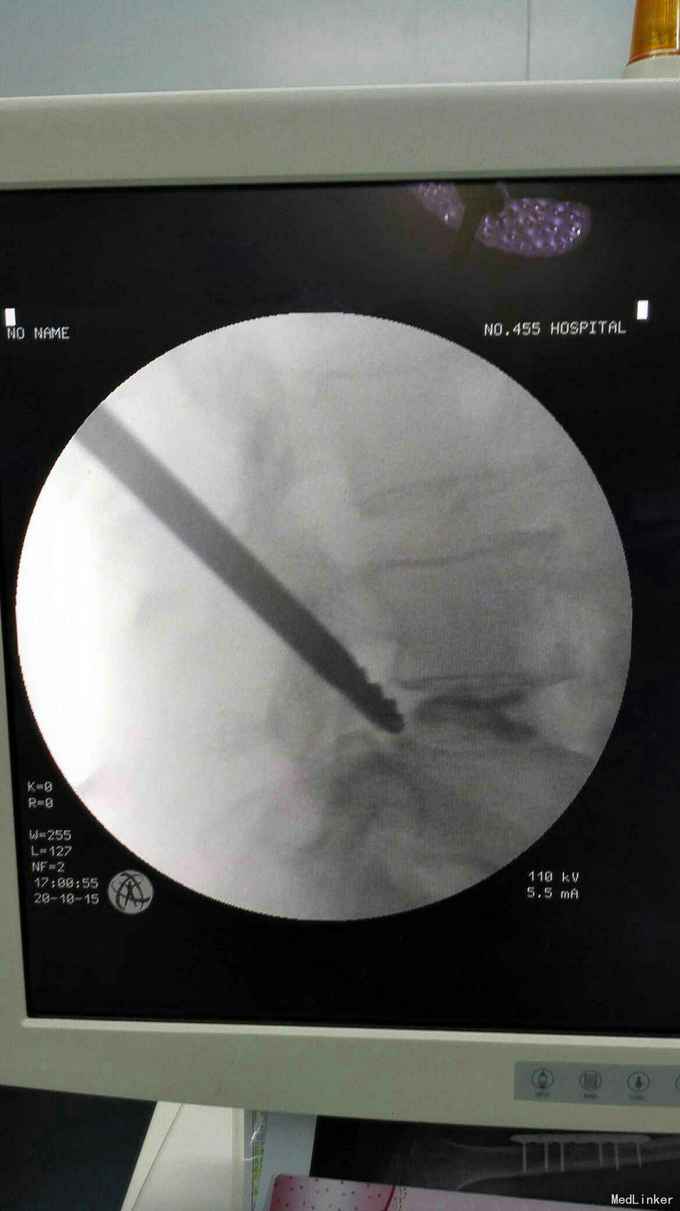

考虑腰椎间盘突出伴椎管狭窄症。行椎间孔镜下髓核摘除,椎间孔成形。

术后患者症状消失。 目前脊柱内镜的应用越来越广泛,随着手术技术的进步可以很好解决部分椎管狭窄的问题。